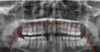

What is represented by orange in the following image?

Inferior alveolar canal

What does the green indicate in the following image?

Mental foramen

What does the green and red indicate in the following image?

Green: external oblique ridge